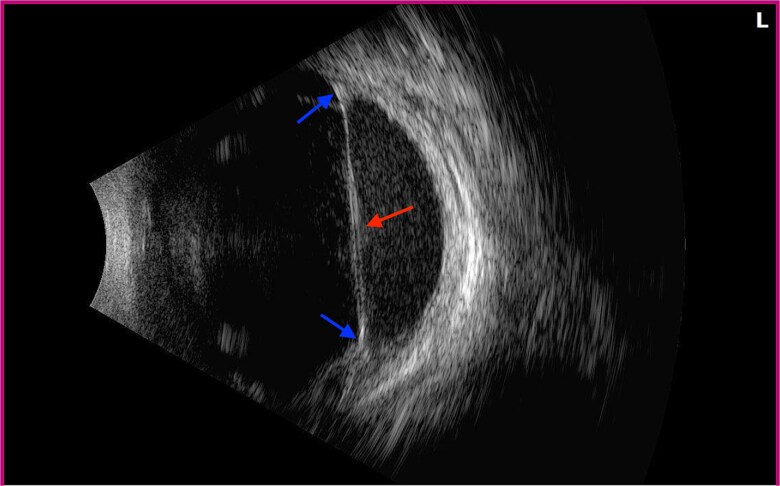

Insect-associated intraocular foreign body (IOFB) is a rare etiology of ocular injury. Ocular exposure to tussock moth hairs, or setae, have been associated with ophthalmia nodosa, endophthalmitis, cataracts, and long-term vision loss. We present a case of a vitreous hemorrhage and tractional retinal detachment induced by Tussock moth cocoon setae. A 12-year-old male suffered a left eye injury induced by Tussock moth cocoon setae, causing vitreous hemorrhage and tractional retinal detachment. He underwent pars plana vitrectomy with removal of IOFB, endolaser, fluid-air exchange, and injection of 14% C3F8 gas. He subsequently developed a visually significant cataract treated with lensectomy, intraocular lens implantation, and yttrium-aluminum-garnet laser capsulotomy, after which he regained 20/20 vision. This case demonstrates a rare occurrence of intraocular moth cocoon setae penetration with severe ocular complications. It also demonstrates the challenges of identifying intraocular setae penetration and treatment approach for successful vision rehabilitation despite delayed IOFB recognition.